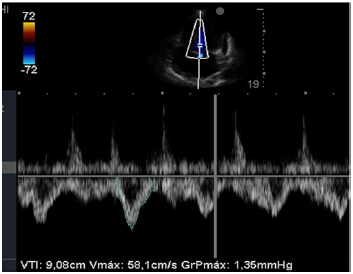

Insonação cardíaca Janela apical 5 câmaras com VTI de 9,08 cm

O nefrologista foi chamado a opinar na melhor conduta para o paciente. Para tanto, realizou uma ultrassonografia beira leito pulmonar e mensurou a velocidade integral tempo (VTI) do trato de saída do ventrículo esquerdo. Chegou, assim, à conclusão que poderia ser feita uma expansão no paciente. Com base nas imagens apresentadas, é correto afirmar que conduta recomendada pelo nefrologista está